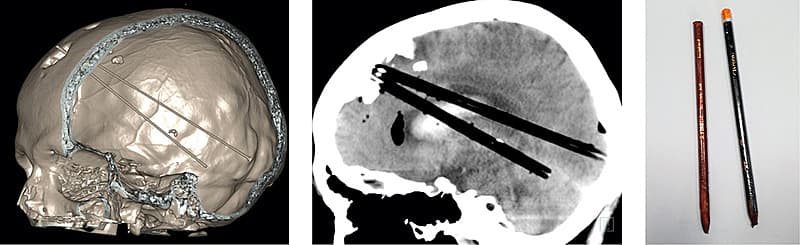

Lukning af forreste tredjedel af sinus sagittalis superior hos en patient med to blyanter i hjernen

En 38-årig mand havde mast to blyanter gennem en eksisterende frontal kraniedefekt, som han ikke tidligere havde ønsket lukket. Han var efter akut overflytning vågen, vurderet psykotisk og uden oplagte neurologiske udfald. Blyanterne var ladt in situ. En CT af cerebrum viste begge blyanter, der strakte sig fra mesialt i venstre frontallap til højre occipitallap og højre cerebellare hemisfære, sidstnævnte via tentorium cerebelli.

Ved en akut kraniotomi fandt man forreste del af sinus sagittalis superior (SSS) penetreret af begge blyanter. For at minimere risikoen for en sinusblødning blev SSS ligeret fortil, inden blyanterne blev trukket ud gennem den frontale defekt.